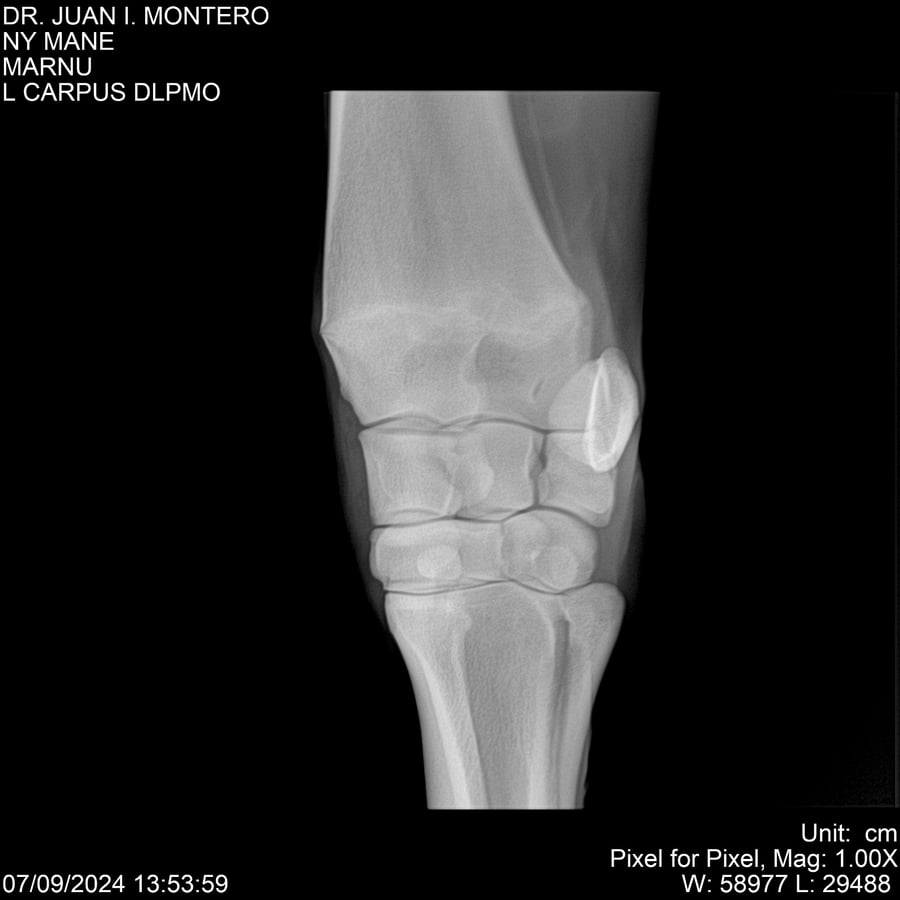

LOTE 20, NY MANE Lote Anterior Volver al remate Lote Siguiente Ficha Contacto Montevideo - Ficha del Lote Identificador: #282520 Categoría: Yeguarizos 76 Visualizaciones ClicData Contacto Empresa: Abelenda N. R., Walter Hugo Nombre*: Teléfono* : E-mail* : Mensaje Enviar Registrese gratis Este contenido Exclusivo está disponible sólo para usuarios registrados Ingresar